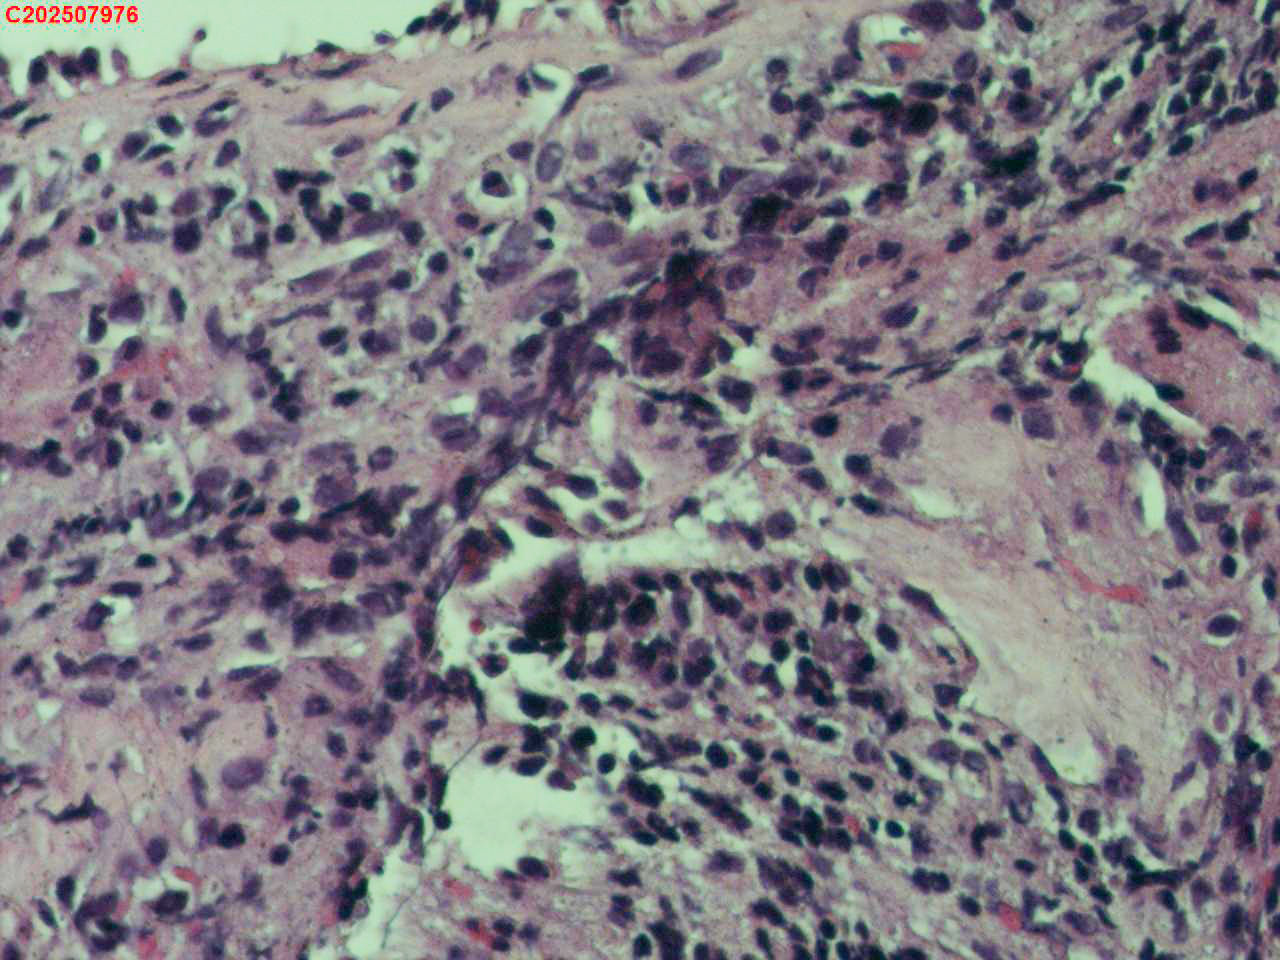

右肺上叶开口处 气管镜咬检

性别

男

年龄

65岁

临床诊断

一般病史

肺TB

标本名称

大体所见

右肺上叶开口上缘处可见肉芽增生,予咬检。

感觉:炎性纤维组织增生